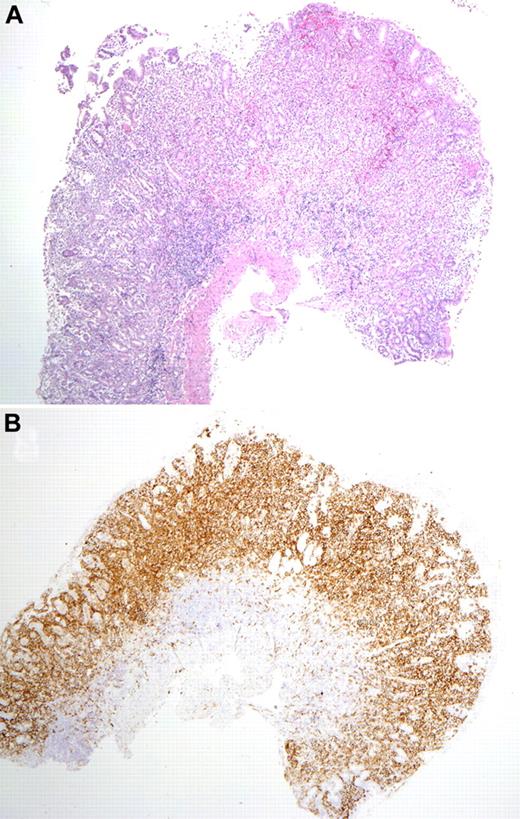

The gastrointestinal biopsies showed similar morphologic features among all patients. There was expansion of the lamina propria by a relatively well-circumscribed but confluent infiltrate of intermediate to large-sized cells with irregular nuclei, inconspicuous nucleoli, finely clumped chromatin, and a moderate amount of pale cytoplasm (Figure 2). In early-phase lesions, the mucosal glands were displaced because of dense atypical cellular infiltrate; however, in advanced stages, sheets of atypical cells with destruction of mucosal glands were noted. There was in general an absence of epitheliotropism identified in glandular epithelium. No angiocentricity or angiodestructive pattern of growth was seen in any patient. Focal infiltration of the submucosa was seen rarely, but in most instances the muscularis mucosa, if observed, was intact. Apart from areas of mucosal ulceration, necrosis was absent, but focal apoptotic bodies were present. Focal superficial hemorrhage was observed in conjunction with some of the infiltrates. A rim of small mature lymphocytes (mainly B cells) and a polymorphous infiltrate of eosinophils, plasma cells, and histiocytes surrounded the atypical infiltrates or was present in the base. In some cases, the adjacent mucosa contained lymphoid follicles. No villous atrophy or crypt hyperplasia was identified in any sample. Peripheral blood and bone marrow specimens obtained (6 of 8 patients) around the time of the gastrointestinal biopsies showed neither atypical cells nor increase in large granular lymphocytes. In 2 patients, additional biopsies of tonsil and lymph node were performed (patients 1, 5). These were histologically unremarkable.

Mucosal biopsy findings. (A) Biopsy of the gastric antrum shows diffuse infiltration of the lamina propria by the atypical cells. The muscularis mucosa is intact, without infiltration of the submucosa. (B) A CD56 stain of the same biopsy highlights the atypical infiltrate. Photomicrographic images were acquired with a Nikon Eclipse 50i microscope equipped with an Olympus DP71 camera and software. Final image preparation was performed with Adobe Photoshop CS3 extended Version 10.0.1. Magnification: 2×/0.1 NA Plan Apo lens.

The atypical cells in the gastrointestinal biopsies expressed CD56, CD7, cytoplasmic CD3, TIA-1, and/or Granzyme B, but not CD5, CD4, CD8, CD10, CD20, CD30, EBV-latent membrane protein (LMP), PAX-5, CD138, or CD68 (Figure 3; Table 2). CD2 was negative in 3 cases and focally positive in one. This immunophenotype suggested an NK-cell origin of the atypical cells. The proliferative fraction as determined by MIB-1 or Ki-67 was low (average ∼ 25%). EBV-encoded RNA was not detected in any patient, by in situ hybridization technique using EBV-encoded RNA probe. Patient 1 had a biopsy of tonsil showing few clusters of CD56+/ CD3+ lymphoid cells in a background of reactive hyperplasia, not thought to be indicative of lymphoma. Flow cytometry was performed on lymphoid cells isolated from the biopsy specimens in cases 1 and 5. The cells failed to express surface CD3 but were positive for cytoplasmic CD3 and strongly positive for CD56 and CD7. The cells were negative for CD4, CD8, and CD5. Because of limited material available in these endoscopic biopsies, flow cytometry was not performed on additional cases. Polymerase chain reaction studies for clonal rearrangement of the T-cell receptor-γ gene were performed in each case and failed to identify evidence of a clonal process.